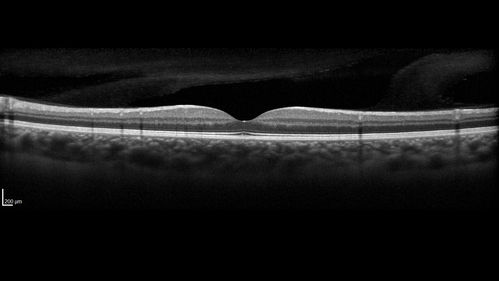

White Retinal Artiole Left eye - Inferotemporal

31 year old female with migraines and headaches for the last 12-13 years. Sometimes she gets the visual symptoms with the migraine. When she gets the migraines the pain is on the left side of her head. She gets the problem a few times a month, sometimes more. They usually last 5-6 hours. She has not had a permanent vision change. When she gets a vision change there are spotty dots of blue neon lights in her vision. With her glasses her two eyes are about the same. VA 20/16 in Each Eye